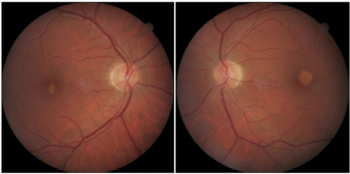

Multiple sclerosis is a neurodegenerative disease with ophthalmic manifestations. Although some cases come to attention following an attack of optic neuritis, embedded optic atrophy can be observed in other, longer-standing cases.

RNFL defects are associated with glaucomatous optic neuropathy and secondary to optic disc drusen.